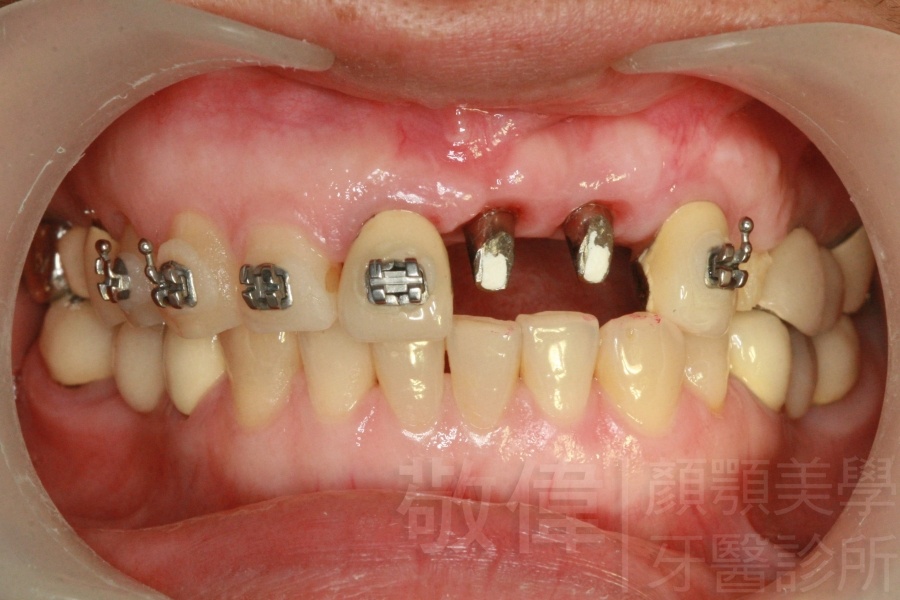

人工植牙/牙周病入侵,牙冠下的牙齒已爛

原來的牙冠底下當支撐的真牙已經爛掉了,造成整排假牙掉下來   植牙的支台柱   金屬燒附陶瓷前牙美容

人工植牙/上顎前牙植牙重建

治療前-缺上排前牙   治療後